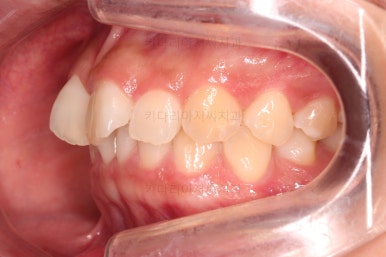

1. 초진

초진 시 입안의 모습입니다.

어금니 쪽은 약간 삐뚤긴 하지만 꼭 교정해야 할 정도는 아니고, 불편감 없이 비교적 잘 맞물리는 상태였습니다.

다만, 앞니ㅉㄱ이 공간이 부족해서 중간 치아들이 많이 회전되어있는데, 이를 환자분들의 표현에 따르면 "나비치아" 라고 부릅니다.

위아래 중간 앞니가 모두 나비치아처럼 되어있고요.

윗니가 아랫니보다 앞쪽으로 나와 있는 모습에 아래앞니가 윗니쪽으로 깊숙이 올라간 "과개교합" 양상을 보였습니다.